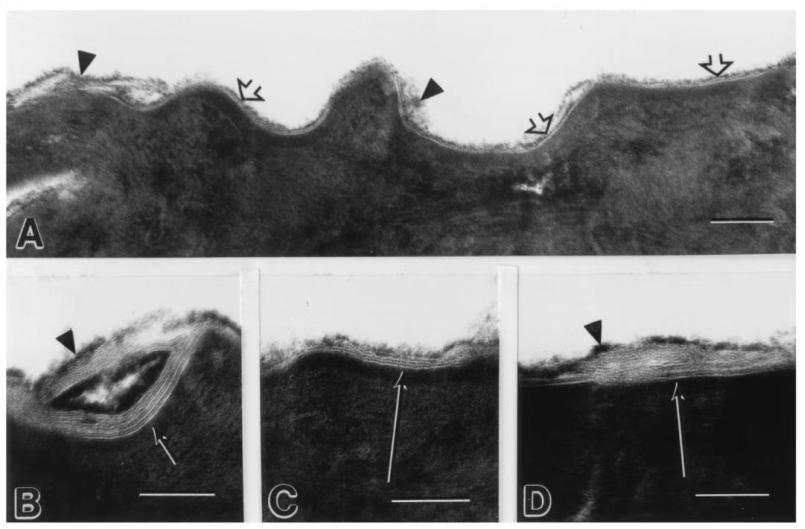

A图:受损的皮肤屏障 B-D图:12周使用神经酰胺后的皮肤屏障

为了更好的修护肌肤物理屏障,这次新品时光美塑脂质液添加了 三重神经酰胺——神经酰胺 NP/神经酰胺 NS/神经酰胺 NG、水杨酰植物鞘氨醇 来完善皮脂膜,促进肌肤保护屏障的修护,提高肌肤的耐受力和抵御力,同时 缓解泛红,维持肌肤稳定,促进皮肤自然水合,强力保湿,及时是在北方的极干环境下,肌肤也依旧水润如初。